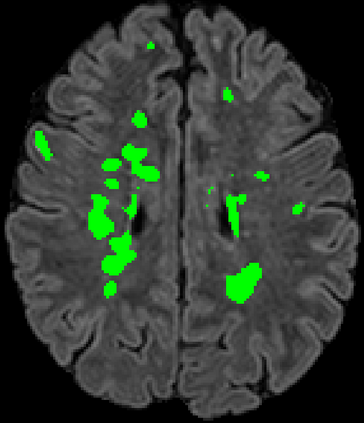

Recently, segmentation methods based on Convolutional Neural Networks (CNNs) showed promising performance in automatic Multiple Sclerosis (MS) lesions segmentation. These techniques have even outperformed human experts in controlled evaluation conditions such as Longitudinal MS Lesion Segmentation Challenge (ISBI Challenge). However state-of-the-art approaches trained to perform well on highly-controlled datasets fail to generalize on clinical data from unseen datasets. Instead of proposing another improvement of the segmentation accuracy, we propose a novel method robust to domain shift and performing well on unseen datasets, called DeepLesionBrain (DLB). This generalization property results from three main contributions. First, DLB is based on a large group of compact 3D CNNs. This spatially distributed strategy ensures a robust prediction despite the risk of generalization failure of some individual networks. Second, DLB includes a new image quality data augmentation to reduce dependency to training data specificity (e.g., acquisition protocol). Finally, to learn a more generalizable representation of MS lesions, we propose a hierarchical specialization learning (HSL). HSL is performed by pre-training a generic network over the whole brain, before using its weights as initialization to locally specialized networks. By this end, DLB learns both generic features extracted at global image level and specific features extracted at local image level. DLB generalization was validated in cross-dataset experiments on MSSEG'16, ISBI challenge, and in-house datasets. During experiments, DLB showed higher segmentation accuracy, better segmentation consistency and greater generalization performance compared to state-of-the-art methods. Therefore, DLB offers a robust framework well-suited for clinical practice.